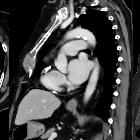

Sternal

metastasis as an initial presentation of renal cell carcinoma: a case report. Thoracic CT scan showing soft-tissue mass in the sternum.